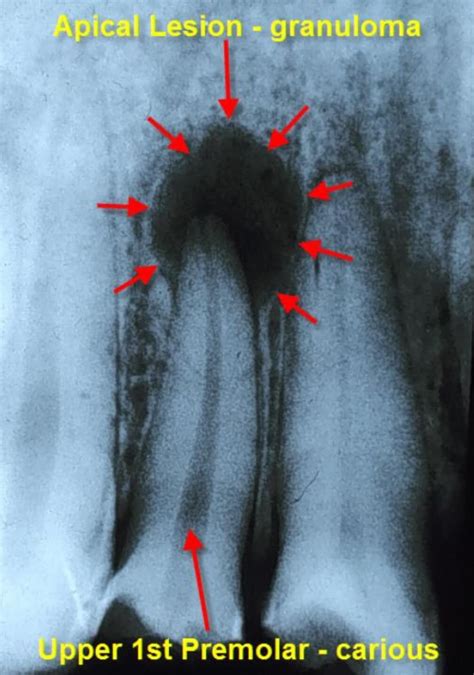

La imagen radiográfica típica muestra radiolucidez periapical bien delimitada, generalmente redondeada u ovalada, con bordes definidos pero no necesariamente escleróticos (a diferencia del quiste radicular). La relación directa con el ápice radicular del diente afectado resulta criterio diagnóstico fundamental, observándose continuidad entre el espacio del ligamento periodontal y la lesión. La lámina dura aparece interrumpida en la zona apical, evidenciando la destrucción localizada de hueso cortical como consecuencia del proceso inflamatorio crónico.